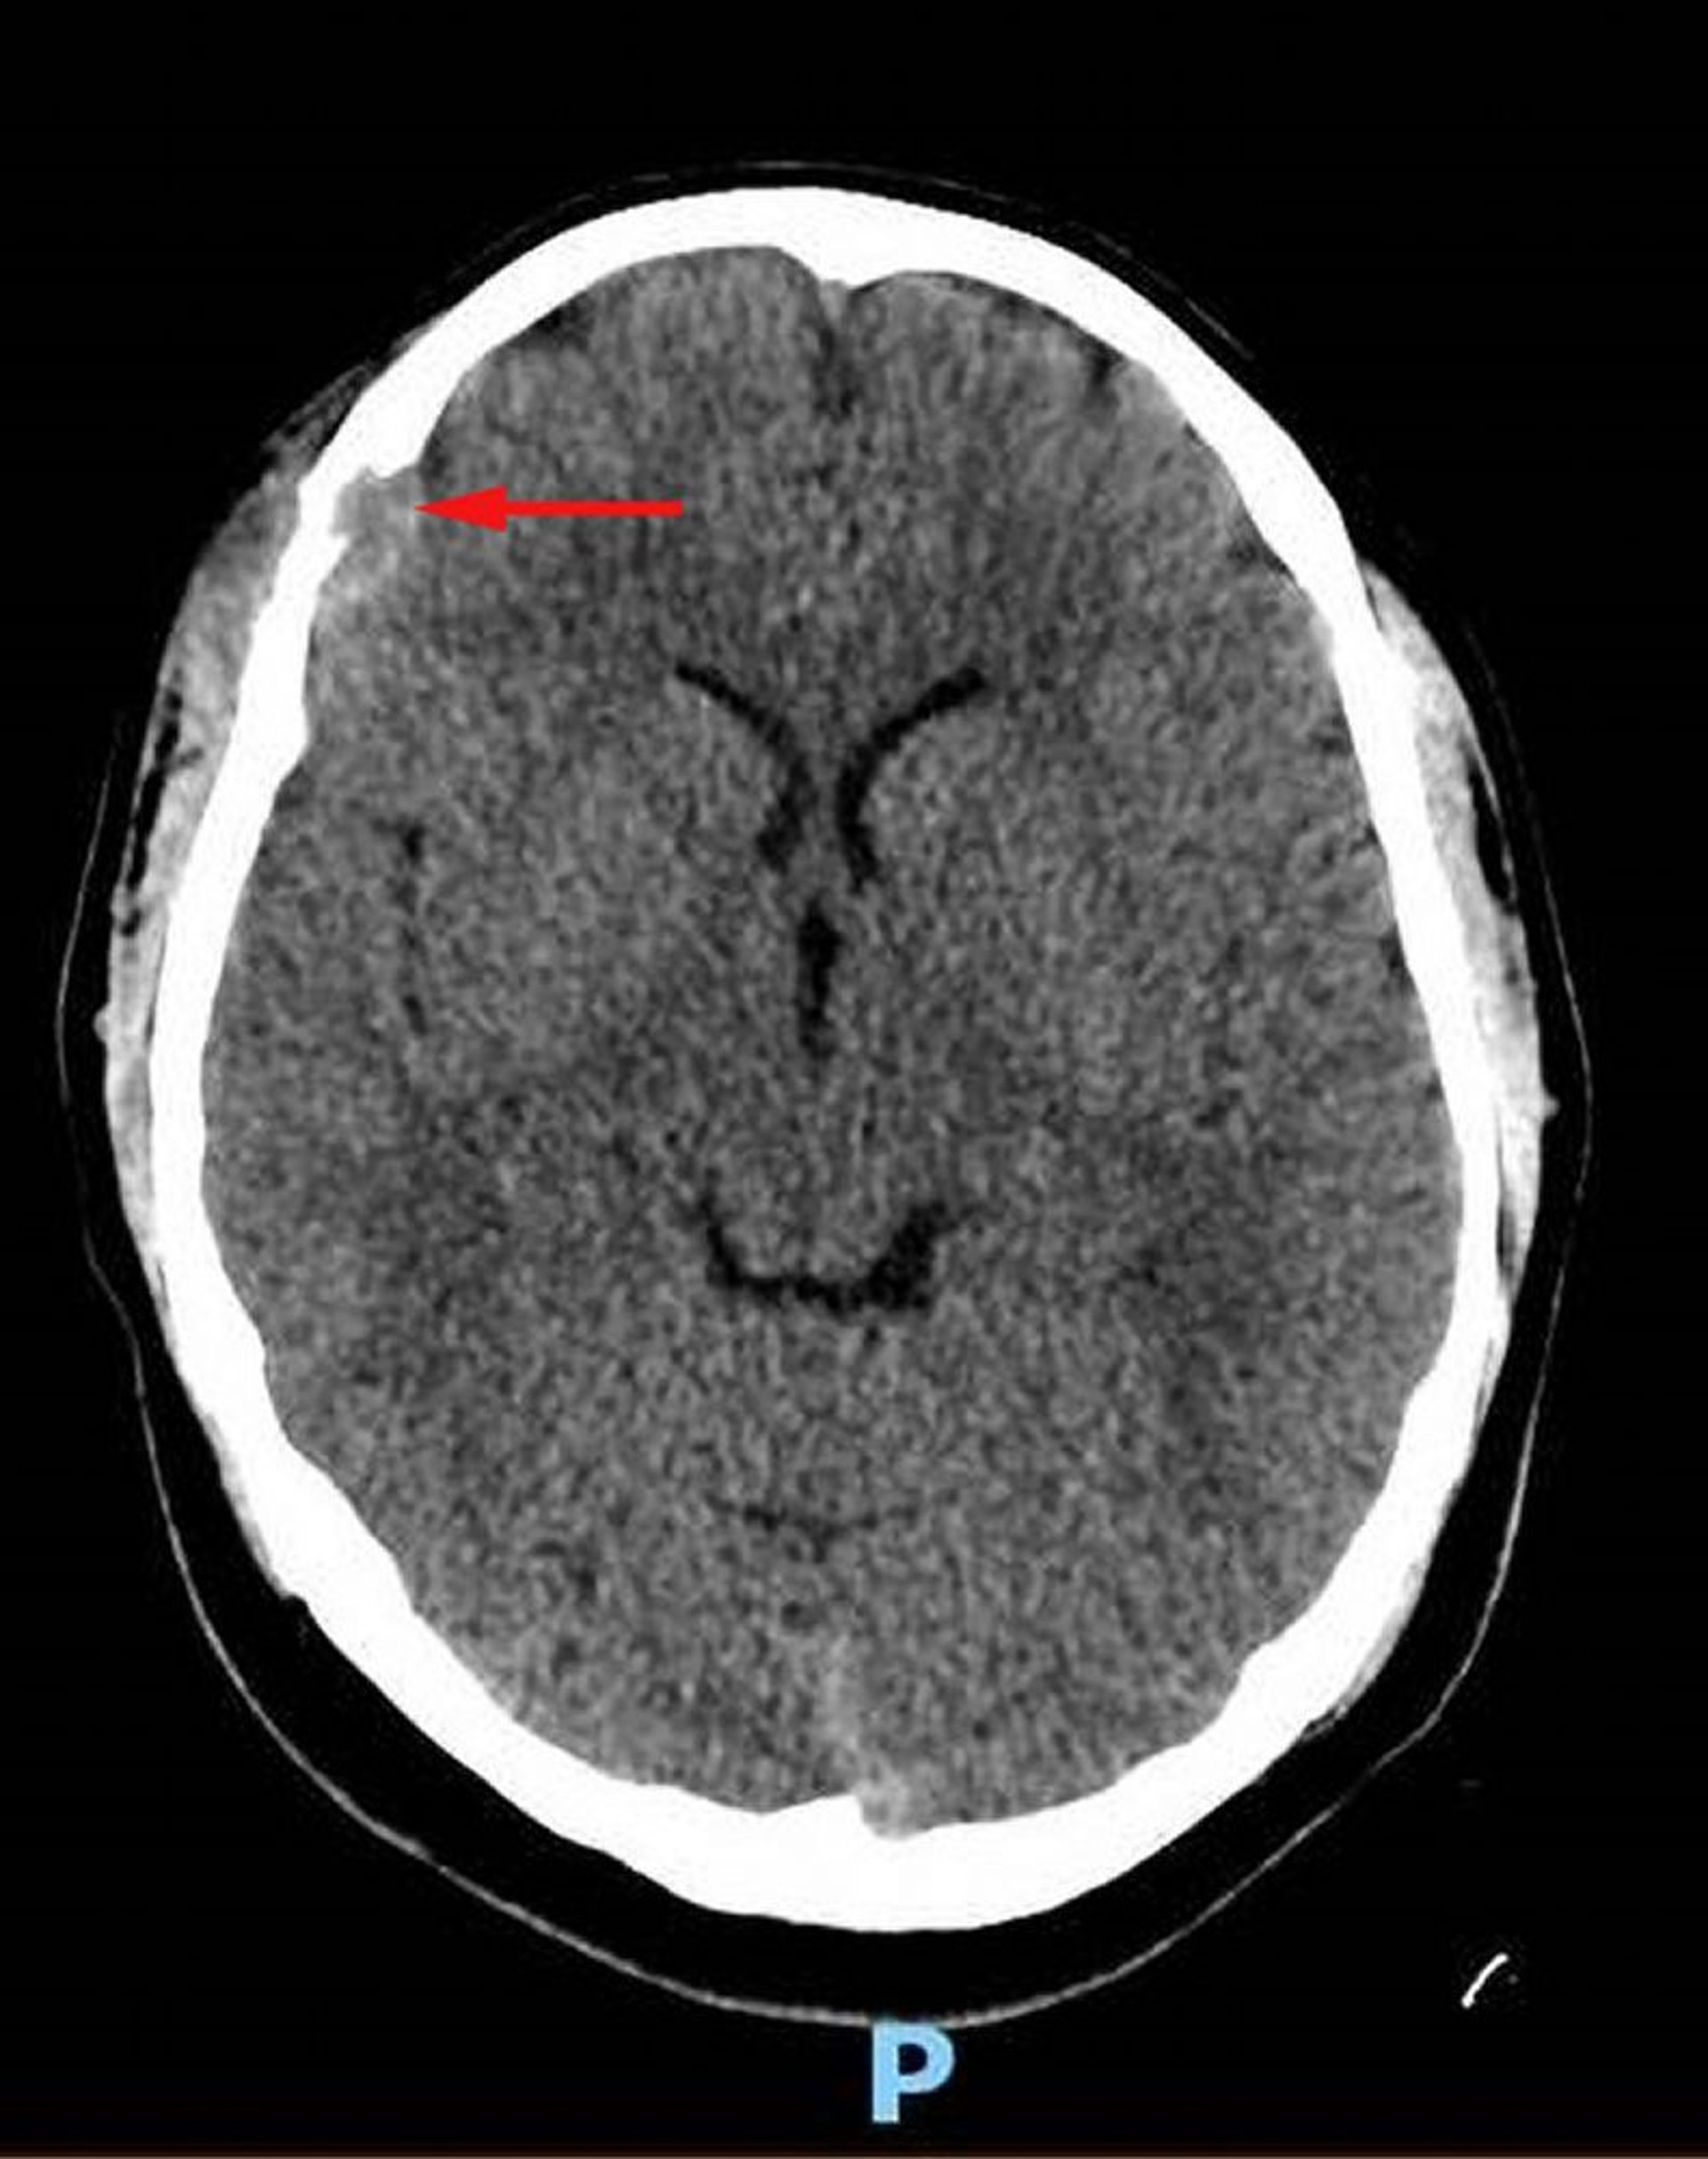

Гістіоцитоз з клітин Лангерганса (КТ голови)

This image shows a soft-tissue lesion in the right frontal bone with associated osseous destruction and intracranial extension of soft tissue into the dural space (red arrow). Asymmetric overlying scalp soft tissue is present. Biopsy was diagnostic for Langerhans cell histiocytosis.

Image courtesy of Carolyn Fein Levy, MD, and Jeffrey M. Lipton, MD, PhD.